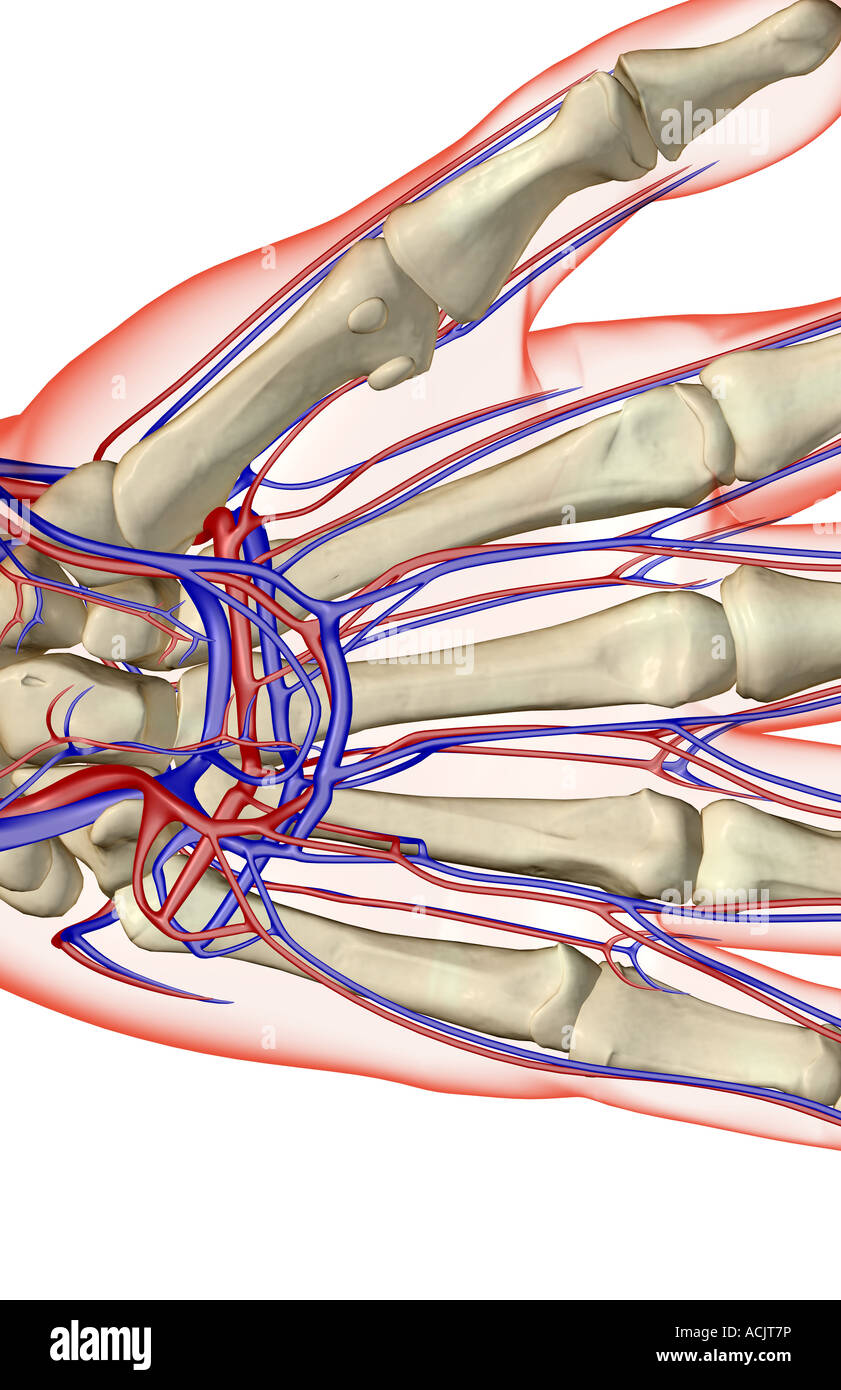

The blood supply of the hand Stock Photohttps://www.alamy.com/image-license-details/?v=1https://www.alamy.com/stock-photo-the-blood-supply-of-the-hand-13173081.html

The blood supply of the hand Stock Photohttps://www.alamy.com/image-license-details/?v=1https://www.alamy.com/stock-photo-the-blood-supply-of-the-hand-13173081.htmlRFACJT7P–The blood supply of the hand